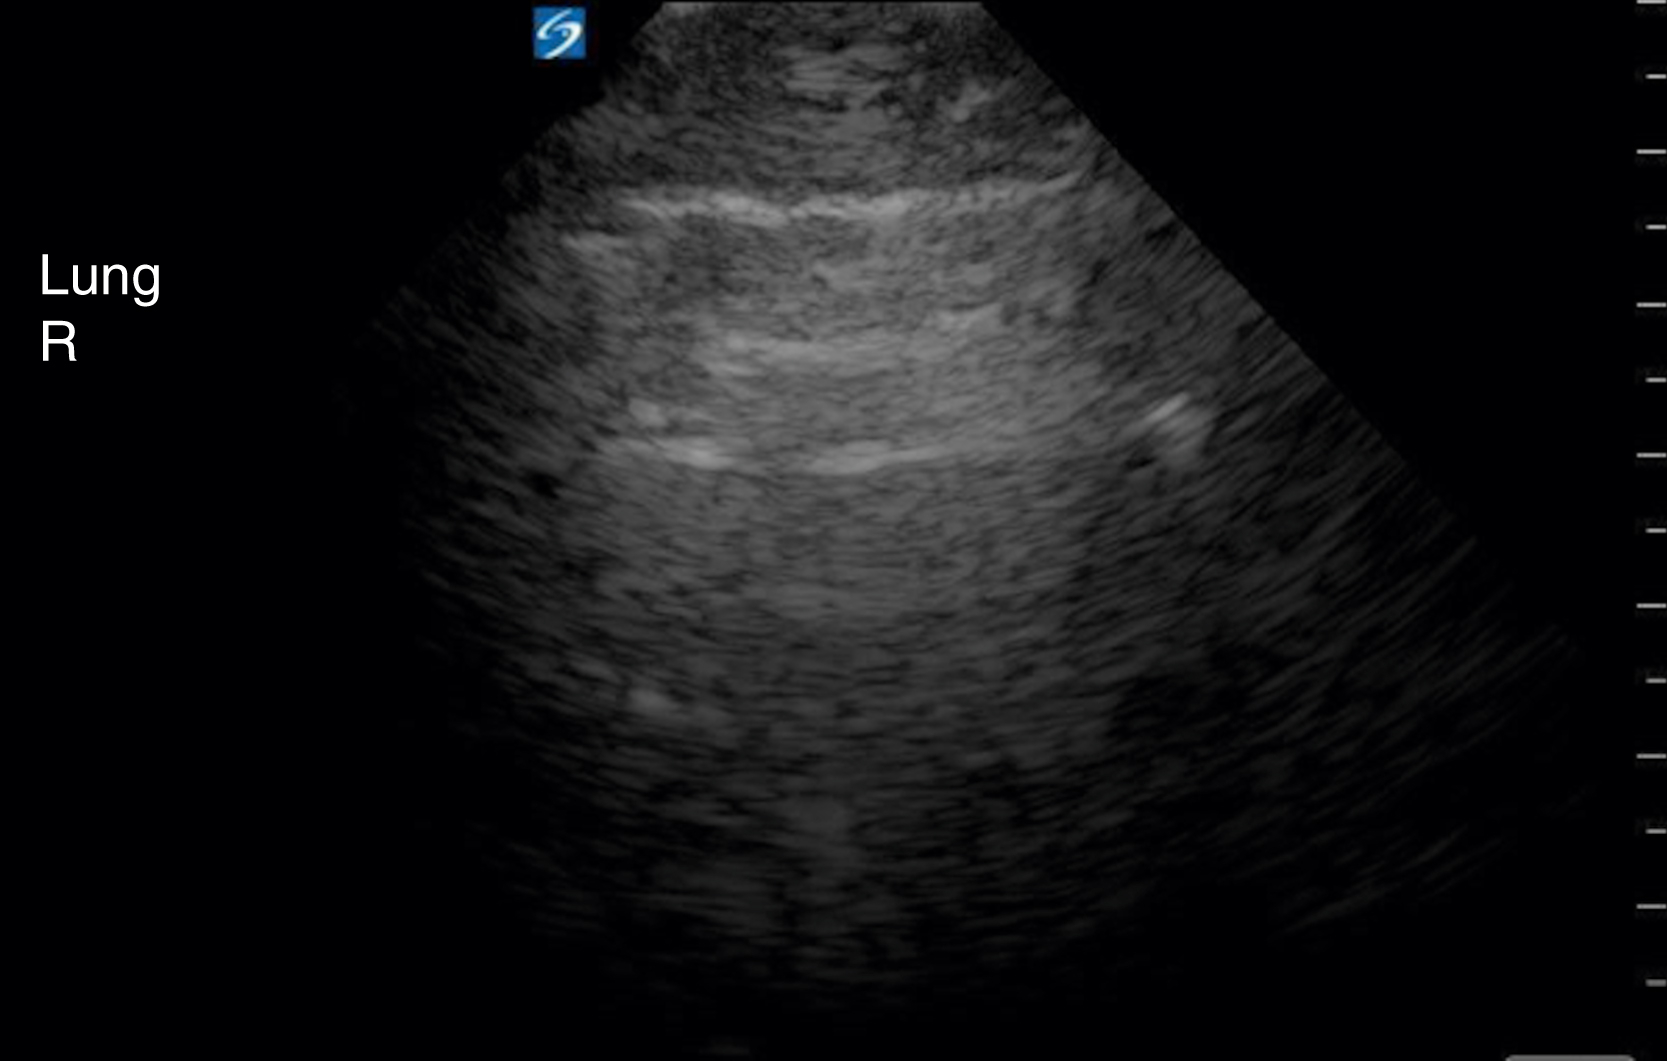

Pathology

The visualization of lung sliding excludes the presence of a pneumothorax at that location on the patient’s chest wall. Although M-mode and color Doppler techniques have been described as adjuncts to the evaluation of patients with suspected pneumothorax, neither is a necessary component of the examination. Absent lung sliding can result from a variety of causes in addition to pneumothorax, including pleural adhesions or consolidations, blebs, pleurodesis, partial or complete pneumonectomy, and contralateral mainstem bronchus intubation ( Fig. e3.15 ). A lung point sign is identified at the border of the pneumothorax, where the image shows absent lung sliding until the lung moves into the interspace with respiration ( Video e3.12 ).

M mode images of the lung. (A) Normal lung with “seashore” sign. (B) Pneumothorax with “stratosphere” or “barcode” sign.